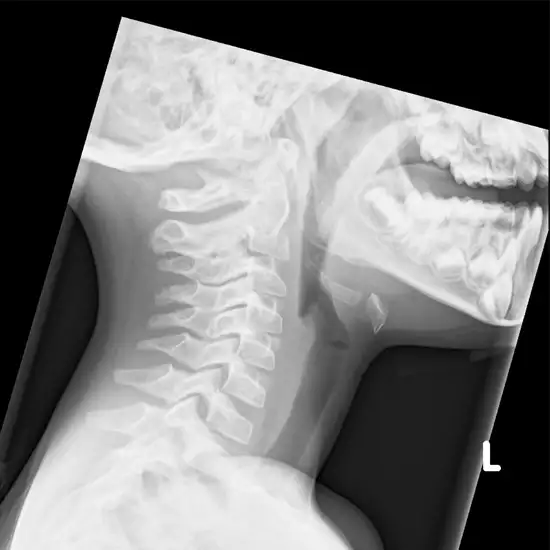

X-ray Soft Tissue Neck LAT View

In order to examine the neck's soft tissues, an X-ray technician will take photographs of the patient's neck from the side (also known as a lateral view).

The X-Ray Soft Tissue Neck, LAT View test is a way to determine what kind of soft tissue injuries a person has in their neck. The X-ray can show problems with the windpipe (trachea), ligaments, tendons, inflammation, severe throat infections, and other muscle injuries.